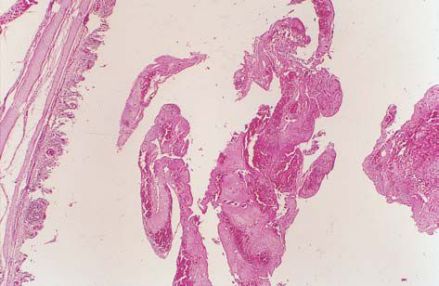

喉头水肿为喉部松弛处的粘膜下有组织液浸润。其病因有感染性和非感染性两大类。感染性喉水肿可因急性喉炎、急性会厌炎、急性喉软骨膜炎、喉部脓肿、喉结核、喉梅毒等以及咽部或颈部的急性化脓性炎症所引起;非感染性喉水肿可因心脏病、肾炎、肝硬化、甲状腺功能低下,过敏性或遗传性如注射青霉素,口服碘化钾、阿斯匹林等药物以及过敏体质者食用致敏食物如鱼、虾、蟹等原因。

症状:喉痛、声嘶、喉喘鸣和呼吸困难,并可伴发热恶寒,咽喉疼痛,喉镜下可见粘膜呈深红色水肿、表面发亮,喘鸣,声嘶,呼吸困难,甚则窒息,喉镜下可见喉粘膜弥漫性水肿,苍白